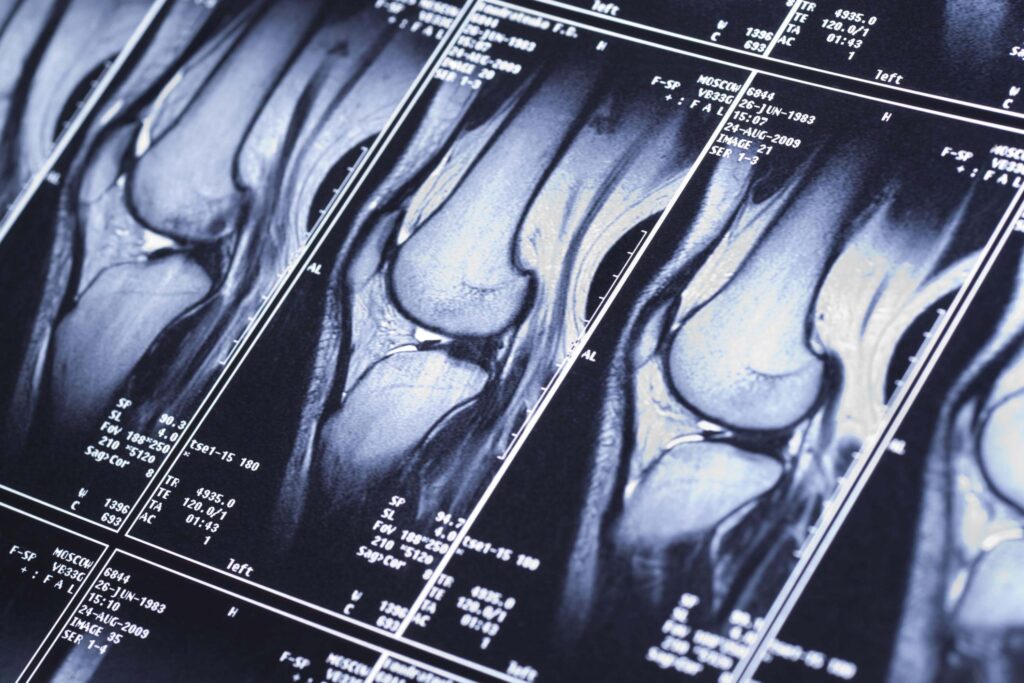

We collaborate with licensed Spanish imaging centres that run the latest 1.5 T – 3 T scanners, calibrated for whole-body and regional studies.

Our partnered clinics use advanced multi-sequence protocols designed for high-resolution anatomical detail and clinical precision—ideal for preventive and diagnostic imaging.

360° body imaging

Our partner radiologists are experienced in full-body imaging protocols, rather than limiting assessments to isolated organs. This collaborative approach provides a broader perspective on your health, offering insights designed to support preventive care.